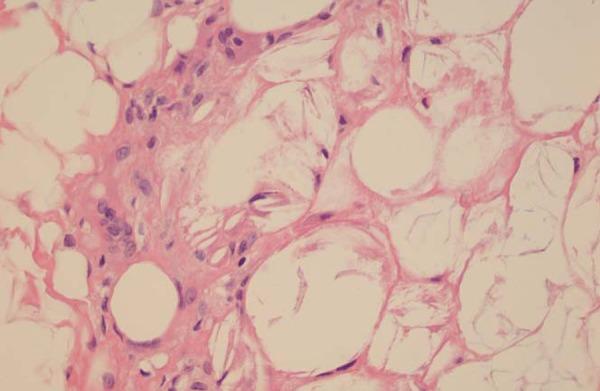

Subcutaneous fat necrosis of the newborn is an unusual form of panniculitis, with few cases described in medical literature. The disease affects newborns at term or post-term, with normal general health. We describe two cases of newborns affected by the disease. One of them already had lesions since birth. Also, we discuss the use of puncture for diagnostic assistance.

新生儿皮下脂肪坏死是一种罕见的脂膜炎形式,医学文献中描述的病例很少。该疾病影响足月儿或过期产儿,一般健康状况正常。我们描述了两例受该疾病影响的新生儿病例。其中一例自出生就有病变。此外,我们还讨论了穿刺在诊断辅助中的应用。